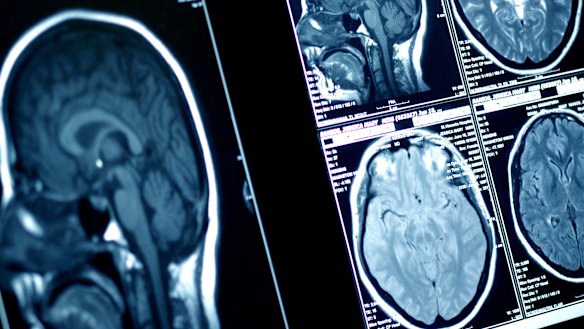

A landmark Australian study found two deceased former league players, both with more than 150 first-grade games of experience, presented with Chronic Traumatic Encephalopathy. It has sparked a flood of pledges to the Brain Bank from former and current players. It may also prompt Tepai Moeroa to do likewise. The Parramatta forward has had several stints on the sidelines as a result of concussions, but has resumed his career after medical clearances.